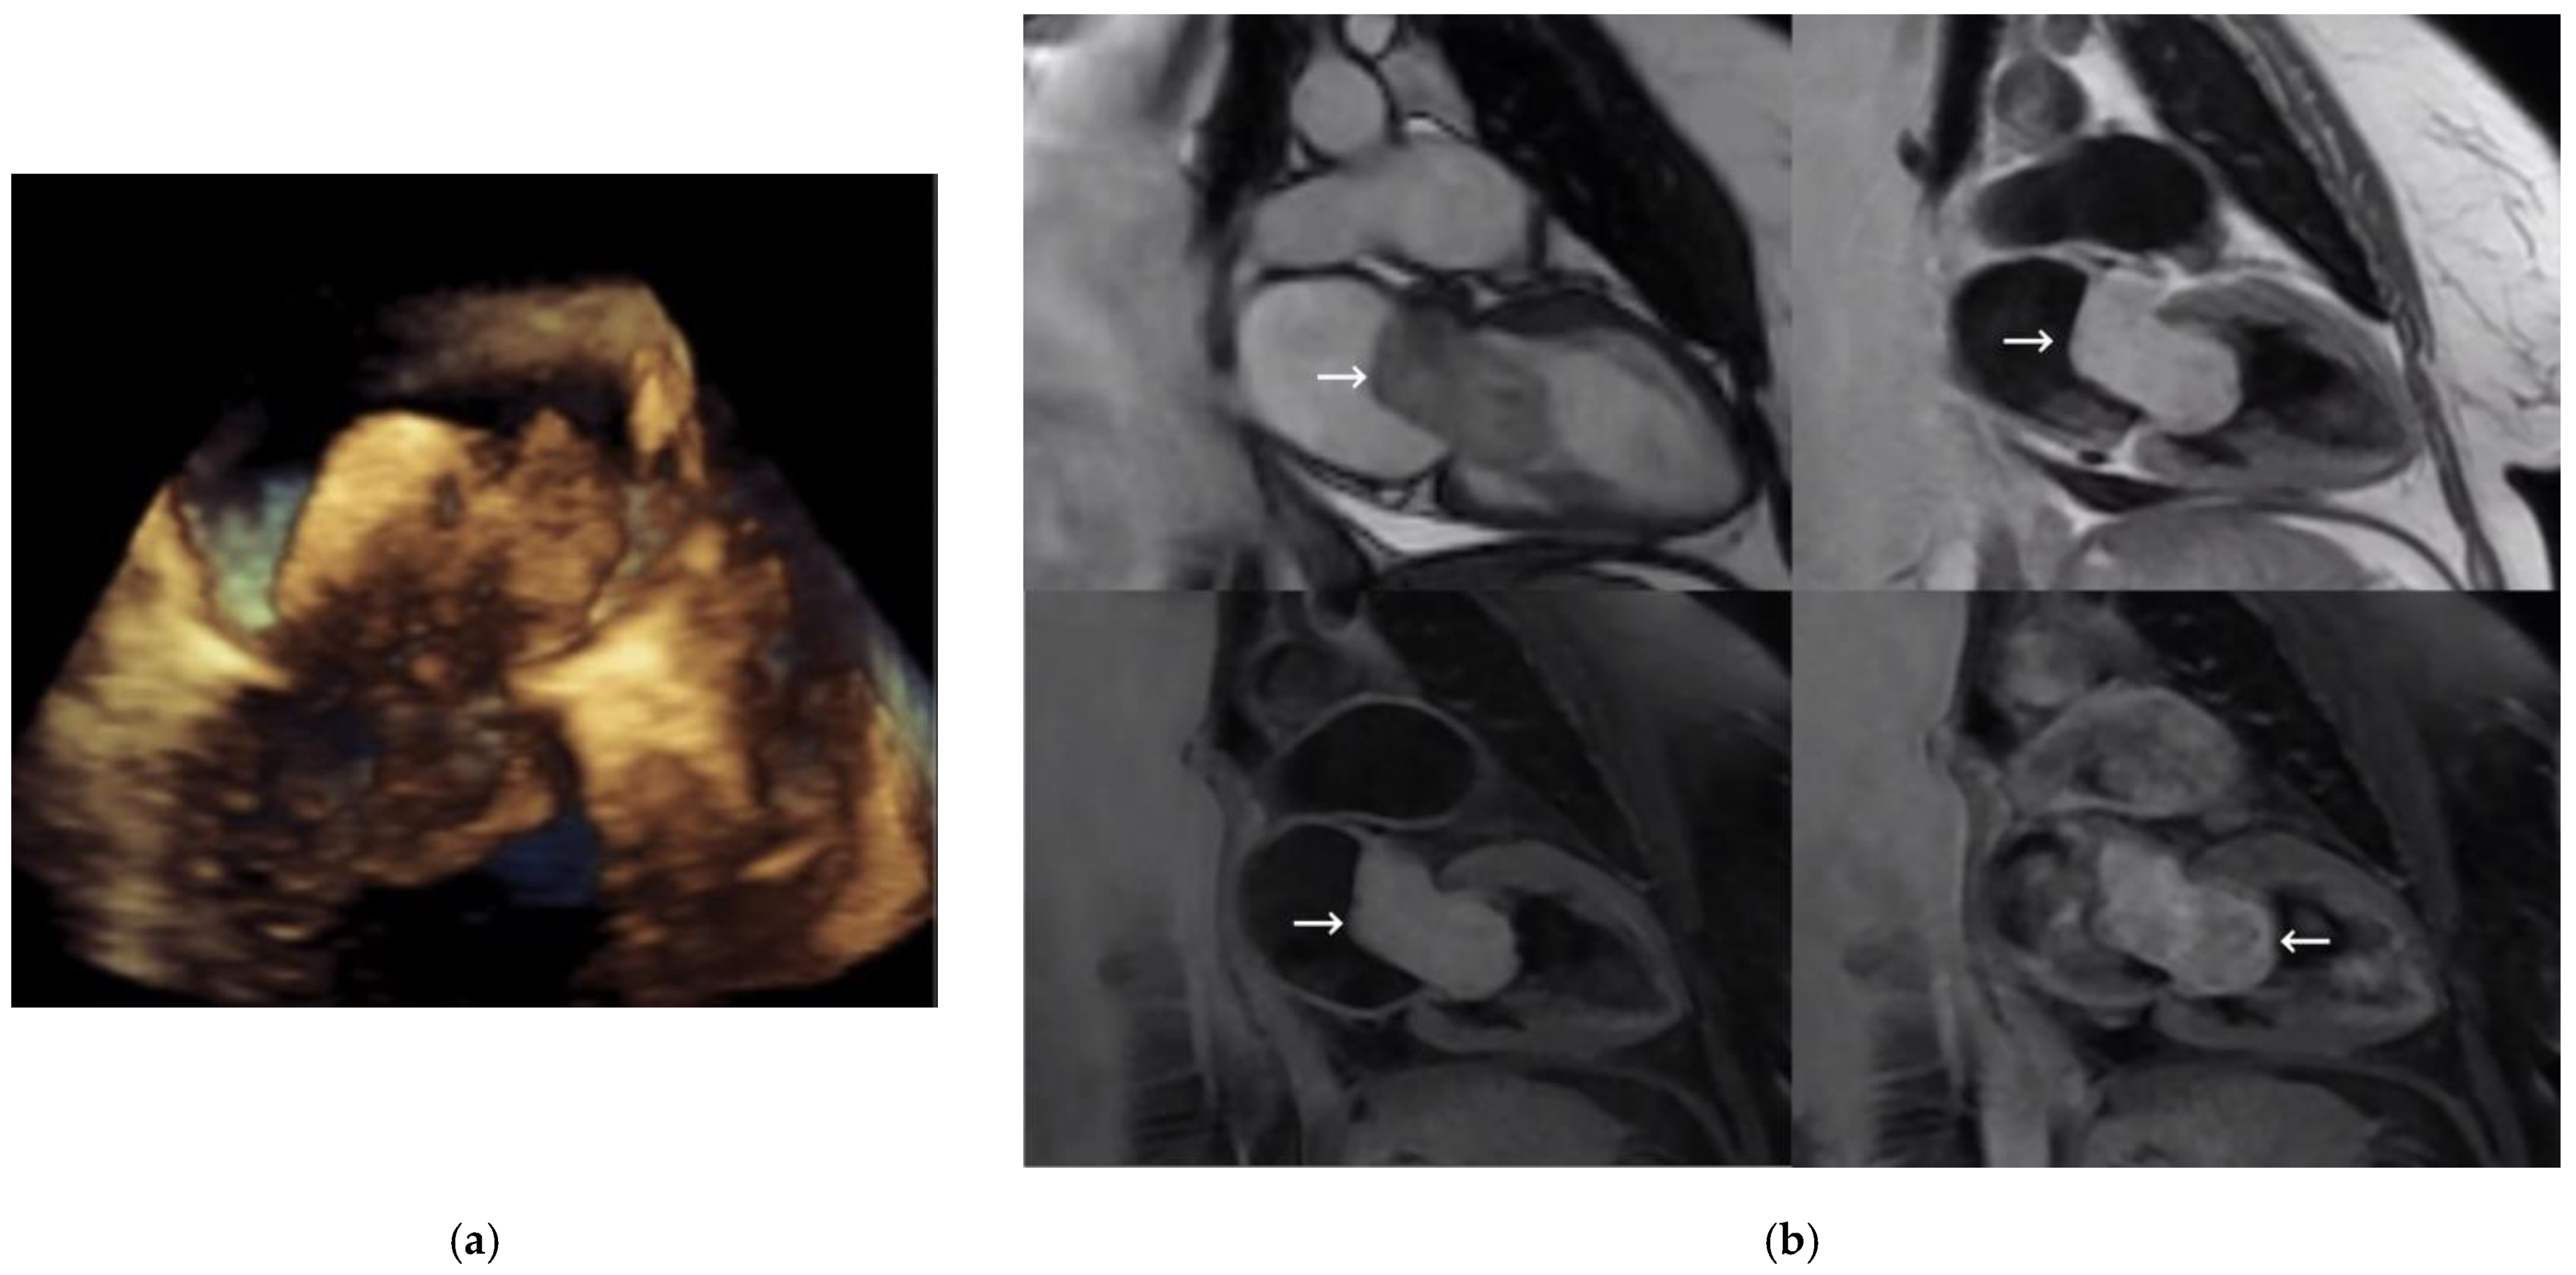

A 58-year-old woman with a history of smoking, hypertension, and type 2 diabetes was examined for dyspnea on exertion after months of evolution. A TTE was performed, revealing a large mass in the left atrium. Two- and three-dimensional TEEs (Figure 1a) showed a 50 × 25 mm heterogeneous, mobile mass attached to the atrial wall in the anterior-retroaortic region (not attached to the interatrial septum) and prolapsing into the left ventricle in diastole, causing severe obstruction in the left ventricular inflow tract. The presumptive diagnosis was atrial myxoma.

MRI, performed for better characterization (Figure 1b), showed an ovoid mass measuring 18 × 23 × 50 mm, with a broad base of implantation on the anterior atrial wall, adjacent to the mitral valve. Fast imaging employing steady-state acquisition (SSFP) sequences showed great mobility of the lesion, revealing its protrusion into the left ventricle, interfering with the function of the mitral valve. The mass was iso/hyperintense on T1 and hyperintense on T2 images, with predominantly homogeneous enhancement after contrast administration. Therefore, the diagnostic impression was atrial myxoma, with papillary fibroelastoma or fibroma as less likely. Coronary angiography demonstrated the presence of severe coronary artery disease in the first obtuse marginal and posterior descending branches. Finally, the Cardiac Surgery Department performed a double intervention with resection of the atrial mass and double aortocoronary bypass grafting. Median sternotomy with pericardiotomy was the surgical approach. Extracorporeal circulation protocol was established and left atriotomy was performed for the atrial myxoma resection and subsequent endocardial repair with loose stitches. A simple suture was used for atria closing. Myocardial revascularization was then performed with a double bridge of a saphenous vein to the obtuse marginal artery and another saphenous vein to the posterior descending artery. The patient’s condition evolved favorably.

Figure 1. (a) Three-dimensional transesophageal echocardiography image of the mitral valve; (b) magnetic resonance imaging showing two-chamber views of SSFP sequence (top left), short T1 inversion recovery (IR) sequence (top right), short T1 IR sequence (bottom left), and short T1 IR sequence with contrast (bottom right). Left atrial mass is marked with a white arrow.